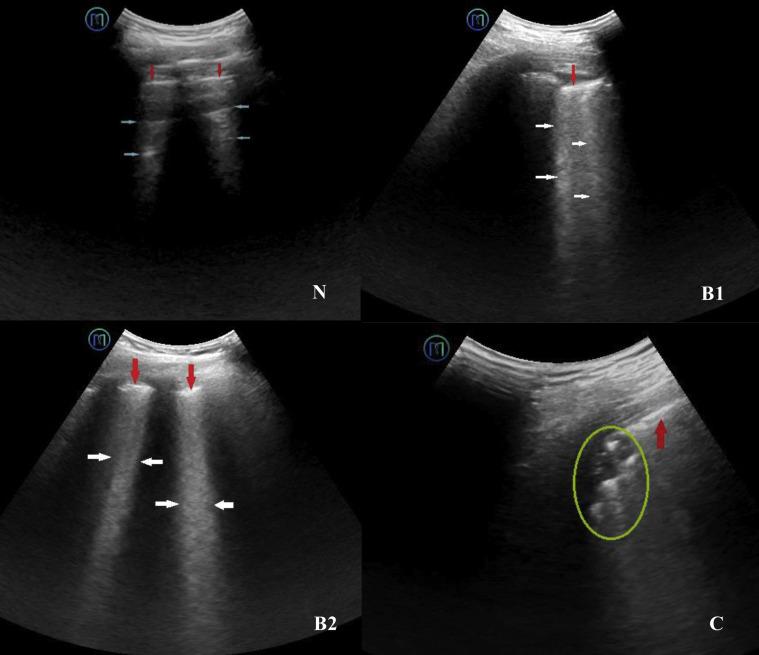

Twenty-three patients with COVID-19 were included and divided into two groups. Twelve were nonsevere cases, and 11 were severe cases. All patients underwent a 5G-based robot-assisted remote ultrasound system examination of the lungs and heart following an established protocol. Distribution characteristics and morphology of the lung and surrounding tissue lesions, left ventricular ejection fraction, ventricular area ratio, pericardial effusion, and examination-related complications were recorded. Bilateral lung lesions were evaluated by using a lung ultrasound score.

The remote ultrasound system successfully and safely performed cardiopulmonary examinations of all patients. Peripheral lung lesions were clearly evaluated. Severe cases of COVID-19 had significantly more diseased regions (median [interquartile range], 6.0 [2.0-11.0] vs 1.0 [0.0-2.8]) and higher lung ultrasound scores (12.0 [4.0-24.0] vs 2.0 [0.0-4.0]) than nonsevere cases of COVID-19 (both, P < .05). One nonsevere case (8.3%; 95% CI, 1.5-35.4) and three severe cases (27.3%; 95% CI, 9.7-56.6) were complicated by pleural effusions. Four severe cases (36.4%; 95% CI, 15.2-64.6) were complicated by pericardial effusions (vs 0% of nonsevere cases, P < .05). No patients had significant examination-related complications.

共纳入 23 例 COVID-19 患者,分为非重症组 12 例和重症组 11 例。所有患者均按既定方案接受基于 5G 的机器人辅助远程超声系统的肺部和心脏检查。记录肺部和周围组织病变的分布特征和形态、左心室射血分数、心室面积比、心包积液和与检查相关的并发症。采用肺部超声评分评估双侧肺部病变。

远程超声系统成功、安全地对所有患者进行了心肺检查。外周肺部病变得到了清晰的评估。COVID-19 重症患者的病变区域明显更多(中位数[四分位间距],6.0[2.0-11.0]比 1.0[0.0-2.8]),肺部超声评分更高(12.0[4.0-24.0]比 2.0[0.0-4.0])(均 P<0.05)。1 例非重症患者(8.3%;95%CI,1.5-35.4)和 3 例重症患者(27.3%;95%CI,9.7-56.6)并发胸腔积液。4 例重症患者(36.4%;95%CI,15.2-64.6)并发心包积液(而非重症患者为 0%,P<0.05)。没有患者出现明显的与检查相关的并发症。